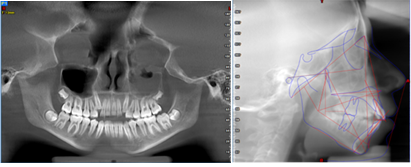

El análisis de discrepancia se realizó sobre los modelos de estudio obteniendo una discrepancia superior de - 4mm y una discrepancia inferior de -1.8 mm (G). En la ortopantomografía se observa que el seno maxilar izquierdo aparece velado, presencia de los 4 gérmenes de los terceros molares, cornetes hipertróficos, no se visualiza ensanchamiento del ligamento periodontal, no existen patologías periapicales (H). Los estudios cefalométricos que se realizaron fueron Rickkets, Jaraback y Steiner, obteniendo como resumen: patrón esqueletal Clase II por protrusión maxilar, a nivel de incisivos: protrusión y proinclinación del incisivo superior e inferior, VERT: +0,69 dándonos un patrón facial: braquifacial suave, en las esferas rotacionales de Jarabak: 54% indicándonos una tendencia a crecimiento rotacional posterior (I).